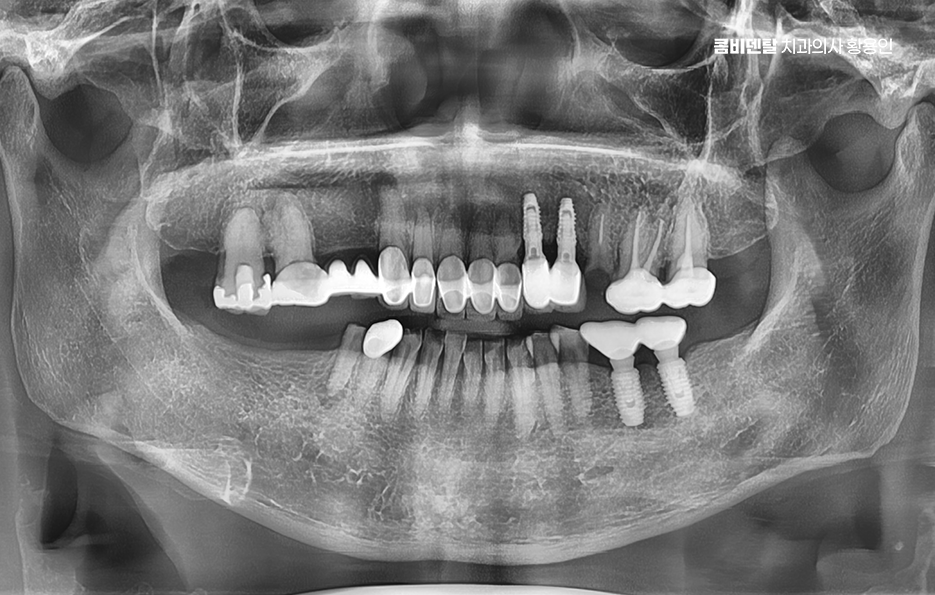

이러한 문제를 막기 위한 효과적인 방법이 바로 임플란트 치료로 어금니 임플란트를 계획할 때는 먼저 잇몸뼈 상태를 정밀하게 확인해야 하며 3D CT 촬영을 통해 뼈의 높이와 두께, 그리고 임플란트를 심을 수 있는 공간을 세밀하게 분석해야 하며 위턱 어금니 같은 경우 상악동이라는 빈 공간이 바로 위에 있어서, 치아가 빠지고 나면 그 공간이 아래로 내려와 임플란트를 심을 자리가 부족해지는 경우가 많고 아래턱 어금니는 하치조신경이라는 중요한 신경이 지나가기 때문에, 신경을 피해서 정확한 위치와 각도로 식립하는 계획이 필요할 수 있어요

결론적으로 어금니 임플란트를 하지 않고 방치하면, 단순히 어금니 하나의 문제가 아니라 전체 교합, 반대편 치아, 나아가 턱관절 기능과 소화 건강까지 영향을 주게 되기 때문에, 가능한 빠르게 치료를 결정하는 것이 장기적으로 더 많은 비용과 시간을 절약하는 방법이 되는 거예요. 특히 뼈가 아직 충분하고, 주변 치아가 건강할 때 임플란트를 진행하면 예후도 좋고, 추가적인 뼈이식이나 부가 수술 없이도 비교적 간단하게 치료가 가능한 경우가 많아서 어금니 상실 후에는 임플란트 치료와의 연계를 잘 고려해서 치료 계획을 늦지 않게 세우시길 바라고 있어요